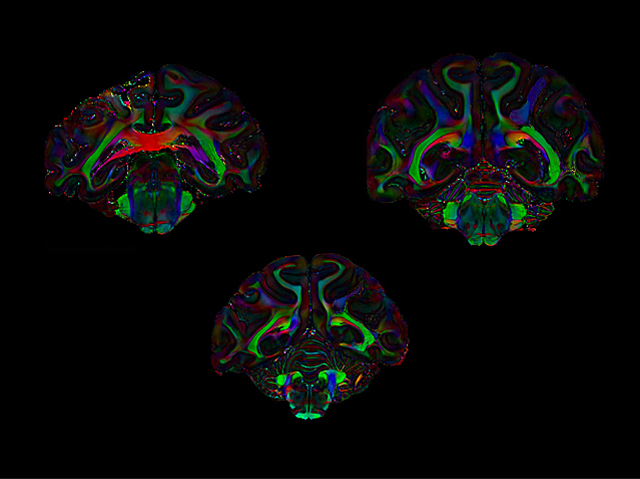

Connections between brain areas involved in attention

Are you paying attention? Good because we’re about to dive into how you do that. Two areas in the upper half of the brain, specifically in the parietal and frontal lobes, are established as important for attention. Recent studies in macaques [species of Old World monkey] have implicated a third region, the posterior infero-temporal dorsal area (PITd). However, the PITd is in the lower half of the brain. Researchers now investigate if and how the PITd connects to the other two regions by imaging macaque brains using diffusion tensor imaging (DTI) (pictured). DTI detects nerve tracts in the brain and revealed that the PITd is indeed directly connected to the two other regions involved in attention via three different tracts. As humans have a brain region equivalent to the PITd, the stage is set to find out if it too is involved in attention, expanding our understanding of the brains’ attention network.